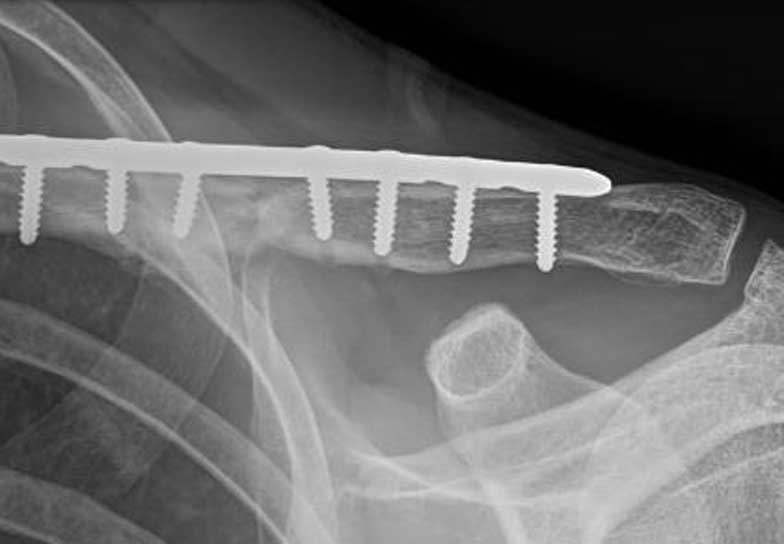

This lady is 65 years old and fractured her clavicle 28 years previously in a motor vehicle accident. At that time she was told that nothing could be done for her. It never really healed and as a result she had ongoing pain in her scapula, shoulder and clavicle. I managed to fix her fracture with a plate and screws and kept her in a sling longer than I normally would and reviewed her for a longer period of time than normal but at her final visit eleven months after her surgery she was delighted with the result as she had no pain, a full range of motion, the fracture was solidly healed and she was doing everything she wanted to do.

Malunion fracture before surgery

Malunion fracture after surgery

Move the slider to compare before surgery and 11 months after surgery